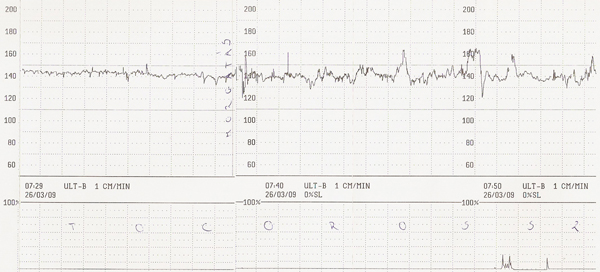

Annus, hoogy megnyugodj, engem ezzel a ctg eredménnyel igaz benn akartak tartani, de csak hogy hátha segítene egy kis magnézium infúzió. Akkor kérdeztem, hogy aki 34 hetesen ilyet produkál, azt hazaengedik? Mondták, hogy igen, na én akkor hívtam a párom, hogy jöhet értem. Szóval, nekem volt egy nagyobb összehúzódás, amit látsz, meg kisebbek alul. De az igazi fájás 120-tól van, azt mondta a szülésznő. (Tudod, ez akkor készült, mikor légszomjjal vebevittek, és több órán át rajtam volt a kütyü, fekvő helyzetben.